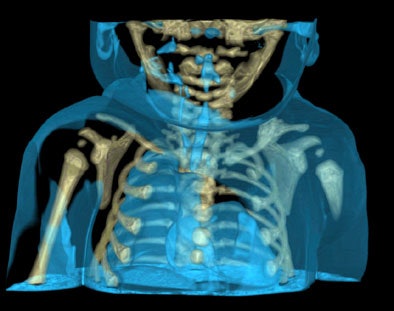

![]() |

| A traffic accident victim suffered from multiple fractures and died from a broken neck vertebra (below). Images courtesy of Dr. Anders Persson and Patric Ljung. |

Air is completely translucent, and serves as a negative contrast agent in postmortem imaging, Persson said in his presentation.